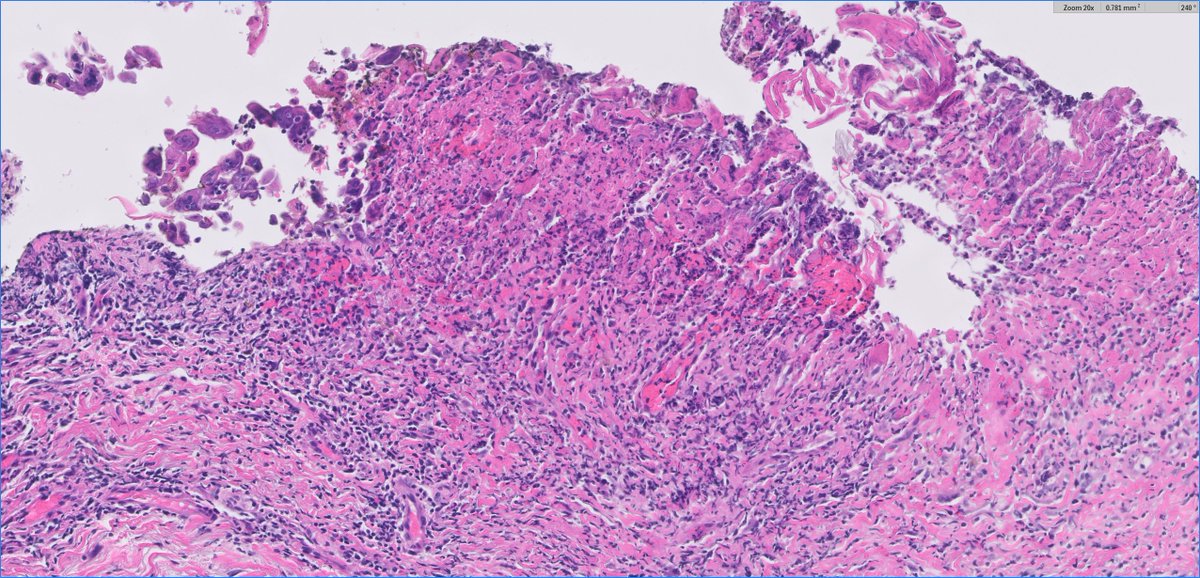

A 62M presents with a 3-month history of dry cough and vague 'heaviness' in his chest. Imaging reveals a 5.2 cm, well-circumscribed, encapsulated mass in the anterior mediastinum. Let's look at the H&E from Low power 🔬 #PathResidents #SurgPath #pathtwitter #pathology

BrownPathology's tweet image. A 62M presents with a 3-month history of dry cough and vague 'heaviness' in his chest. Imaging reveals a 5.2 cm, well-circumscribed, encapsulated mass in the anterior mediastinum.

Let's look at the H&E from Low power 🔬

#PathResidents #SurgPath #pathtwitter #pathology